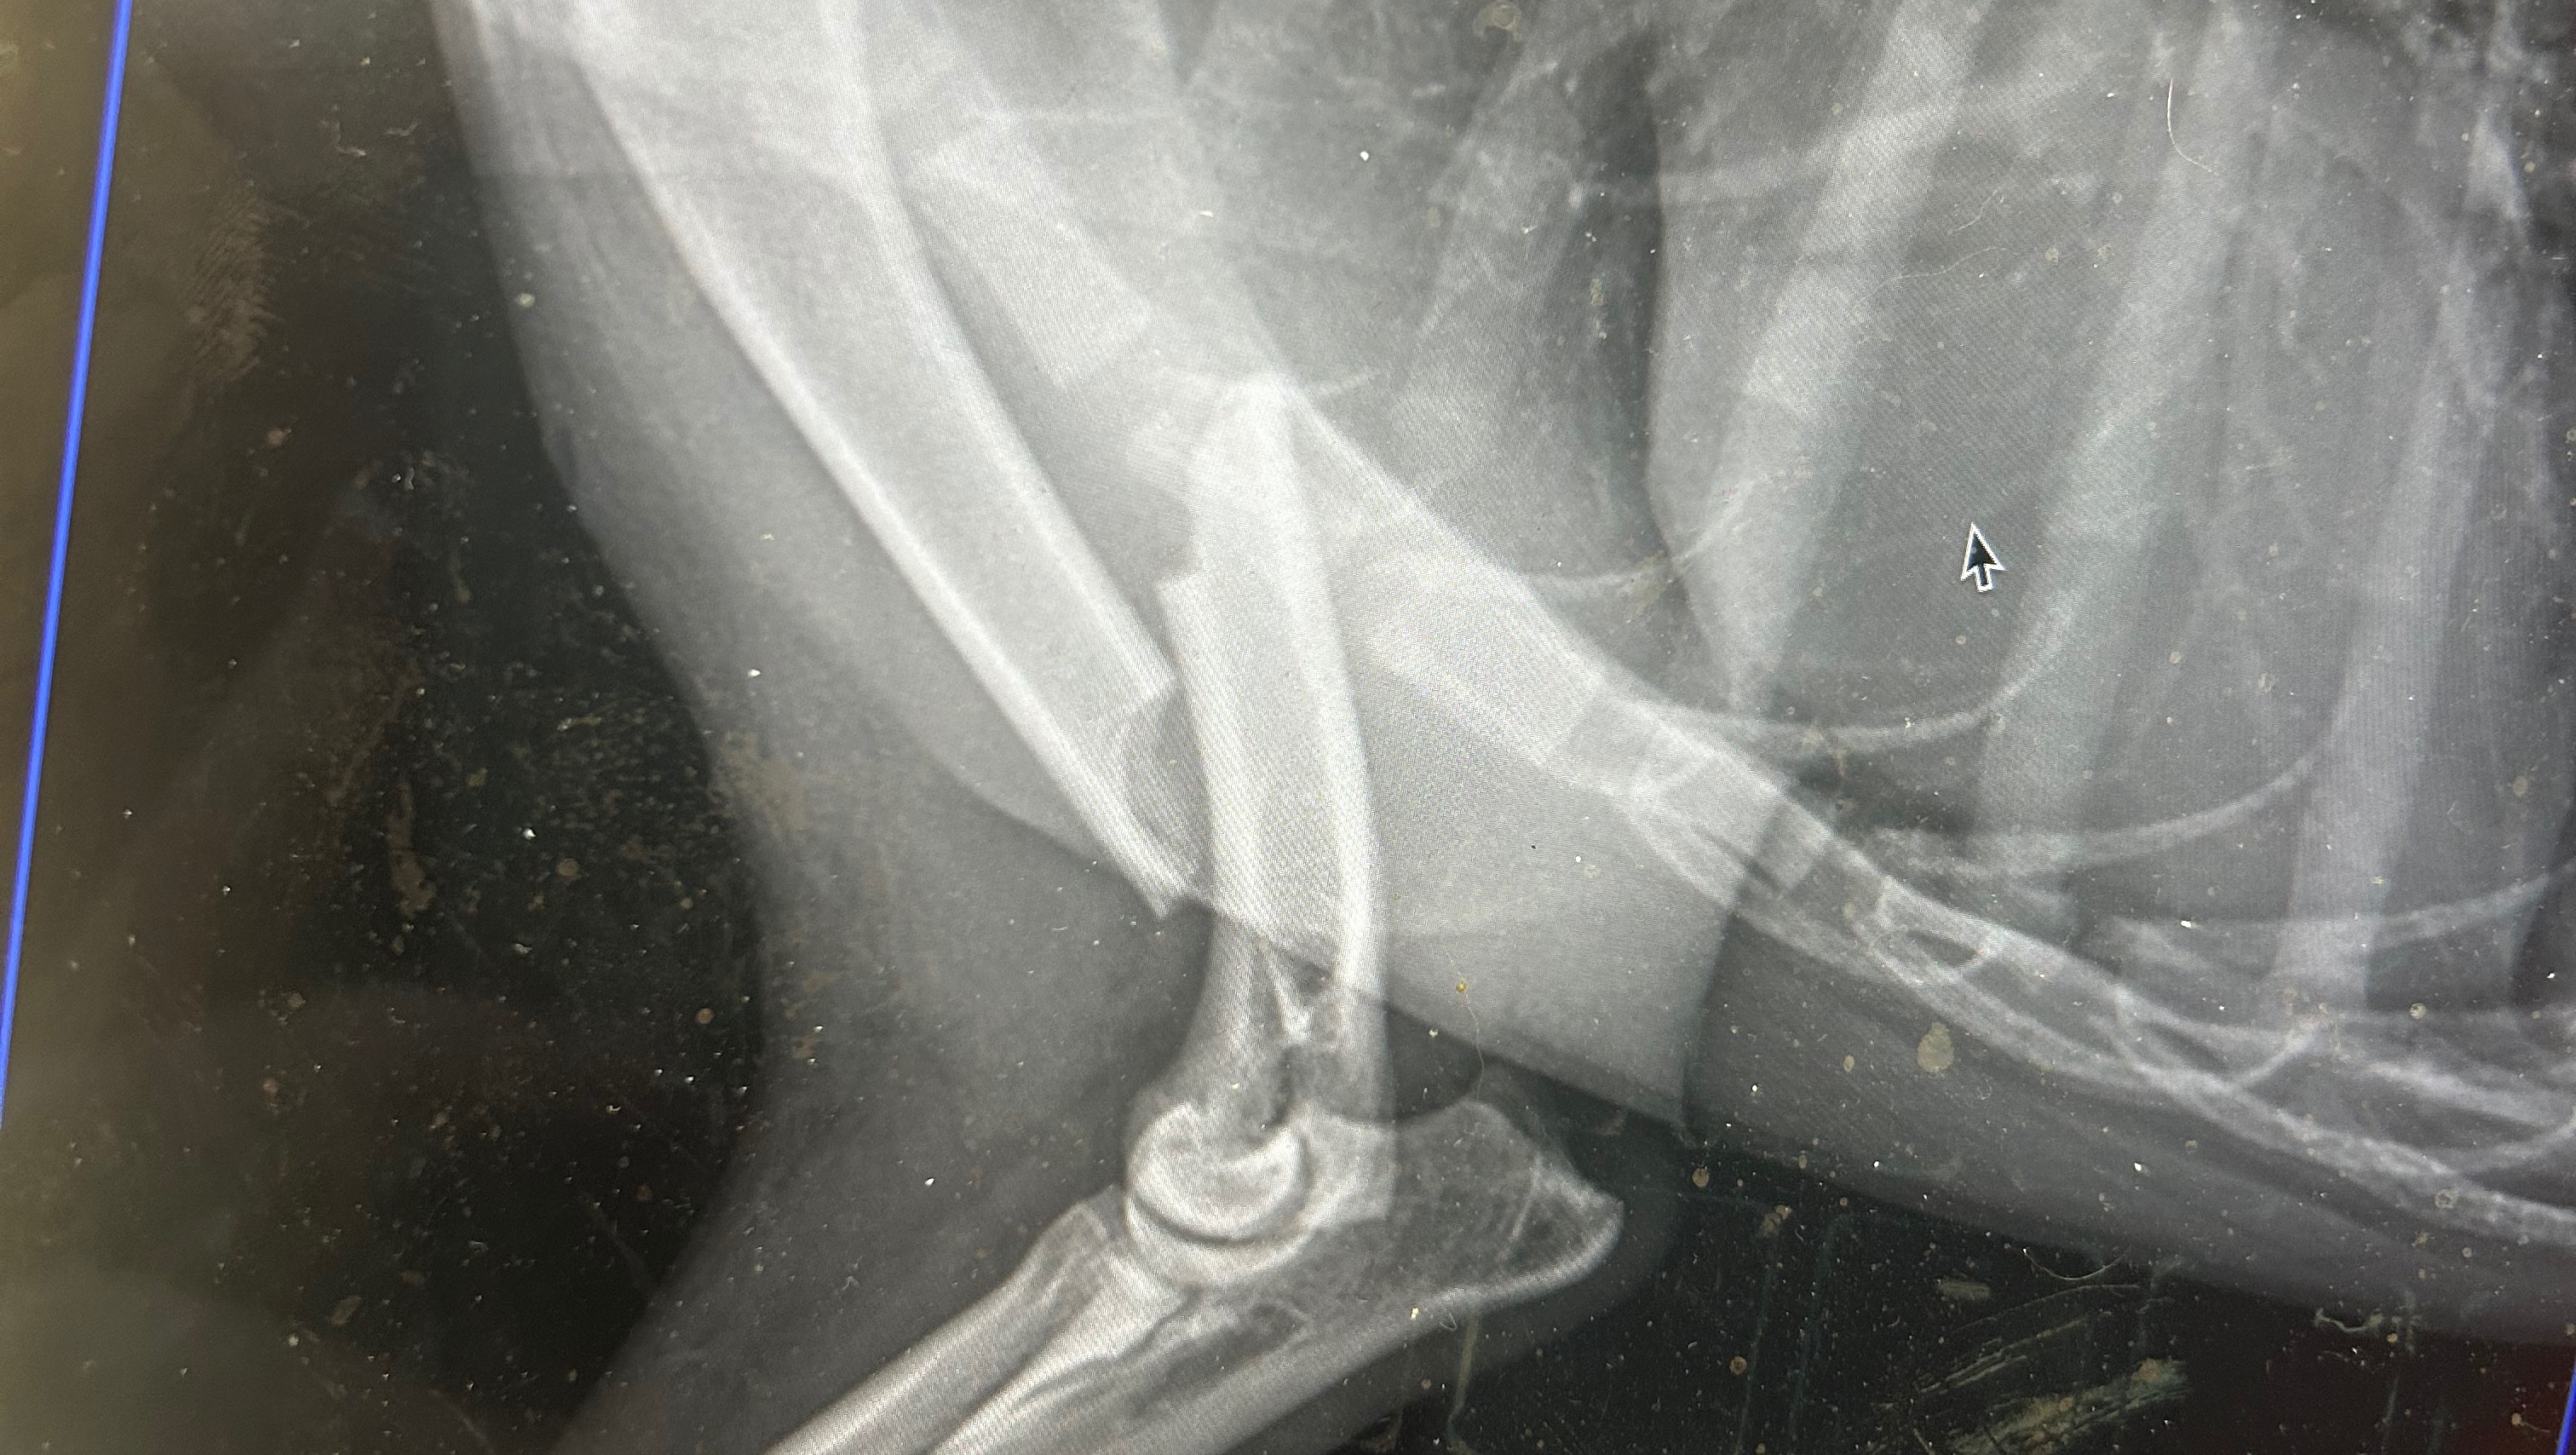

UPDATE: UT called this morning and said it would between 3500-4000

Yesterday, one of our pups, Cali, that we are working to adopt to her forever home, was kicked by a horse. She has a very clean but severe break in her shoulder and will require surgery! However, this surgery is approximately $6000, possibly more depending on the severity of the surgery, and there is no denying it, we just don't have it.